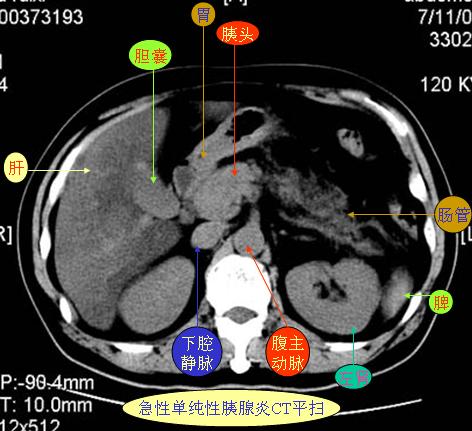

腹部ct解剖与基本病变